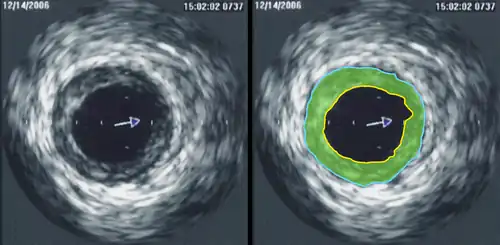

Intravascular ultrasound (IVUS) uses a specially designed catheter with a miniaturized ultrasound probe attached to its distal end, which is then threaded inside a blood vessel. The proximal end of the catheter is attached to computerized ultrasound equipment and allows the application of ultrasound technology, such as a piezoelectric transducer or capacitive micromachined ultrasonic transducer, to visualize the endothelium of blood vessels in living individuals.[12]